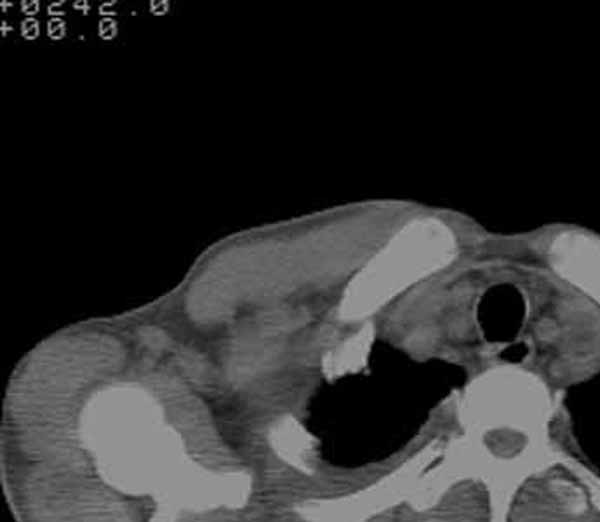

以下是引用余辉在2009-3-31 18:43:00的发言:[br]肺水肿,双侧心腔积液,心包积液,心影增大,疑似心衰

以下是引用wangyong1977在2009-3-31 20:46:00的发言:[br]肺水肿,双侧胸腔积液,心包积液,心影增大,疑似心衰 [br]

以下是引用宇宙ct在2009-3-31 18:57:00的发言:[br]肺水肿,双侧心腔积液,心包积液,心影增大,疑似心衰 [br] [br]